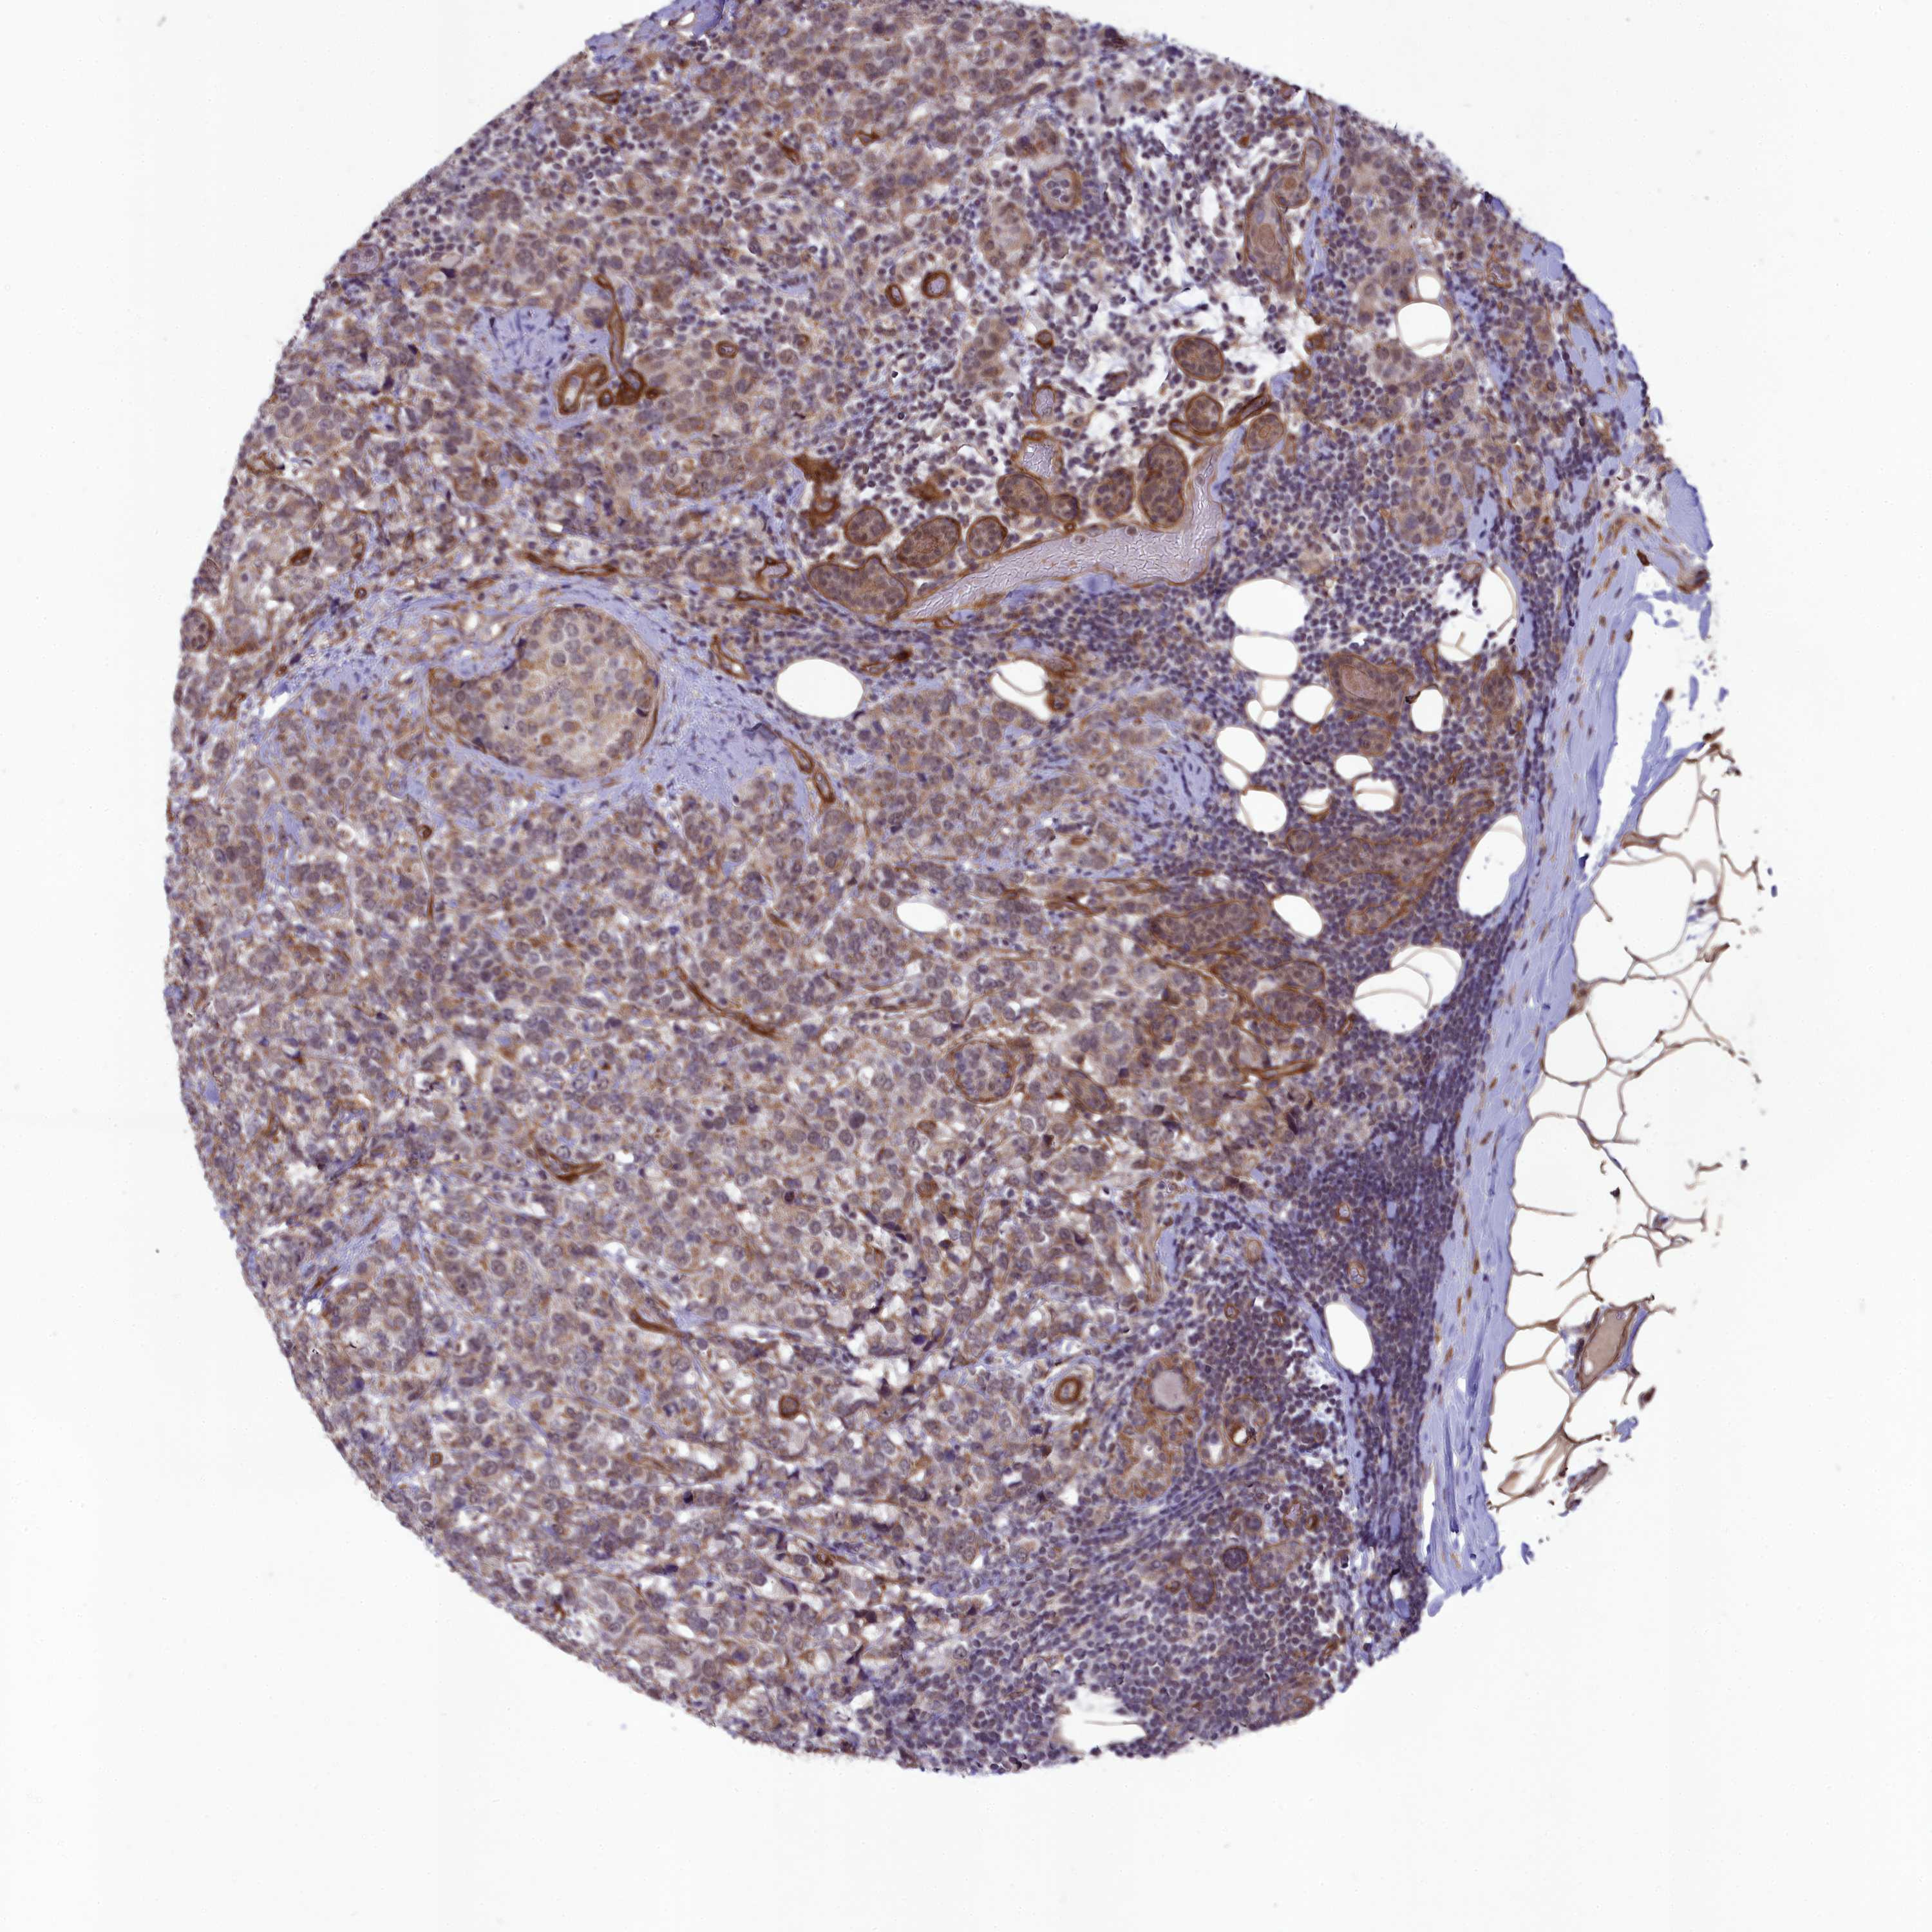

CANCER BREAST CANCER Show tissue menu

BRCA TCGA BRCA VALIDATION PROTEIN EXPRESSION